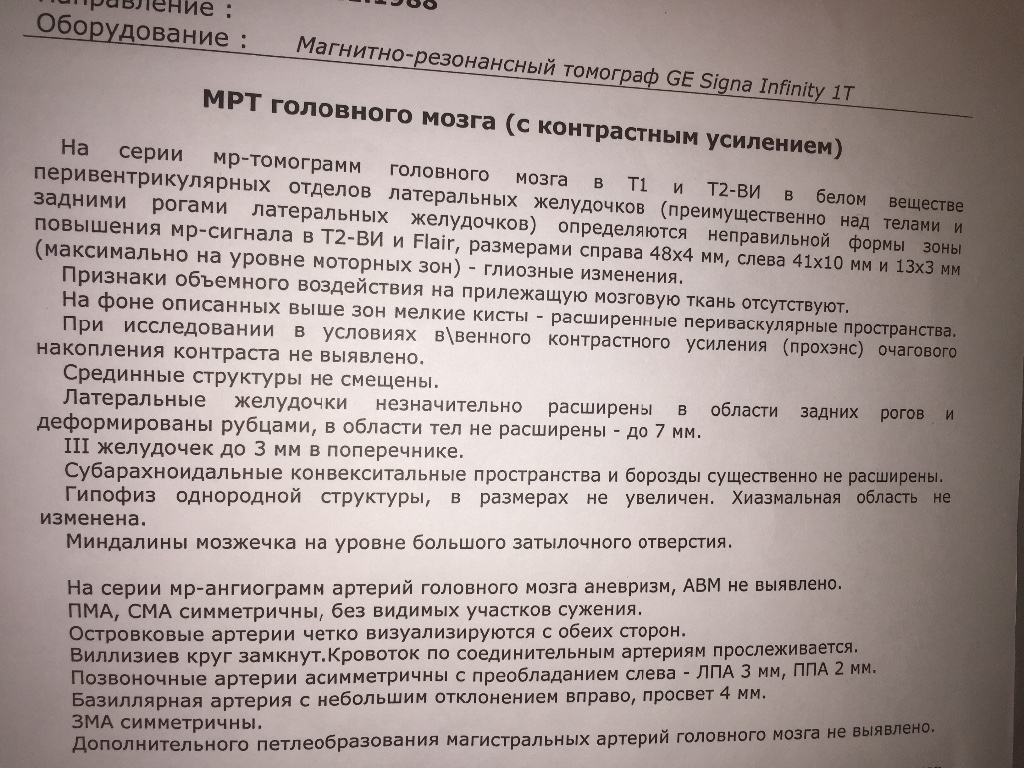

МРТ головного мозга: Расшифровка снимков и Интерпретация

Раздел: Визуальные уроки